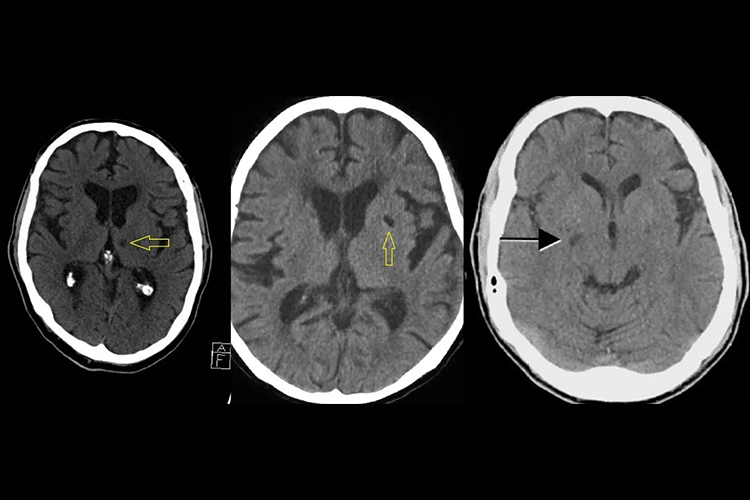

3、颅脑CT:

- 是脑梗死的首选影像学检查方法,能够早期判别脑梗死与脑出血,且检查时间较短,不受患者身上有人工关节、起搏器等限制条件影响。

- 但颅脑CT对于脑干位置显示可能不清晰,且对发病时间较短或较小的病灶可能无法很好显示。